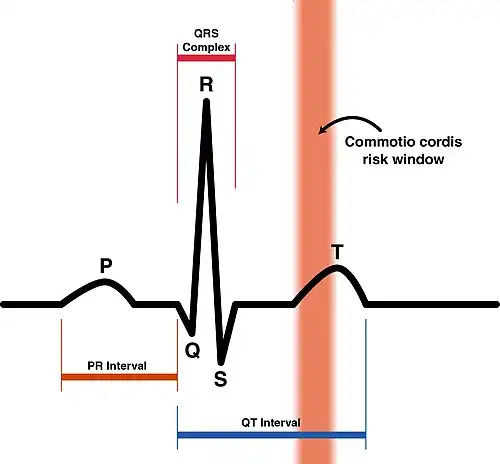

| Causes | Sufficient blow to the precordium between 10 and 40 milliseconds before the peak of the T wave portion of normal cardiac rhythm |

The deviation of commotio cordis from the normal electrical rhythm of the heart is assessed scientifically in laboratory studies by analysis of the electrocardiograph (ECG) T wave (see ECG image).[1] Only chest impacts occurring on a narrow band of the ECG during the upslope of the T wave (40 milliseconds (ms) before the peak of the T wave to the instant of the actual peak) will cause the ventricular fibrillation of commotio cordis, with an increased probability occurring when an impact happens from 30 to 10 ms before the peak of the T wave.[1]

- Impact occurring within a specific 10- to 30-ms portion of the cardiac cycle. This period occurs in the ascending phase of the T wave when the left ventricle is repolarizing, moving from systole to diastole (relaxation).

The small window of vulnerability in the cardiac electrical cycle explains why it is a rare event.[1] Considering that the total cardiac cycle has a duration of one second (for a base heart rate of 60 beats per minute), the probability of impact trauma within the window of vulnerability is 1–3 percent only.[1]